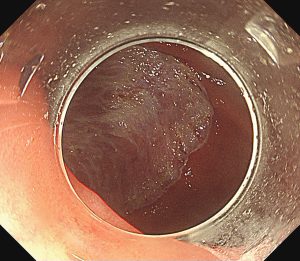

早期胃癌(SM浸潤がん)ESD

早期大腸癌(LST-G)ESD